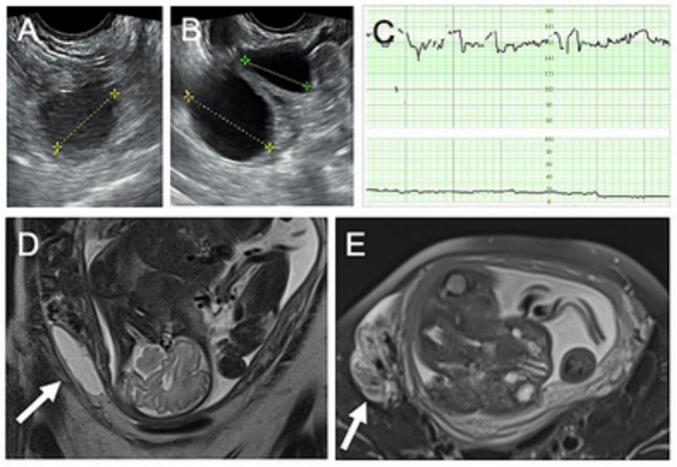

A 39-year-old woman (gravida 2, para 1) presented at 7 weeks of gestation. Her obstetrical history was significant, with previous premature delivery due to cervical incompetency at 36 weeks of gestation. Asymptomatic bilateral ovarian cysts were identified at the initial examination, 23 mm in diameter on the right (Fig. 1A) and 37 and 21 mm in diameter on the left (Fig. 1B), in addition to a viable fetus in the uterine cavity, and observation followed.

Fig. 1.

(A) Ultrasonographic findings of the right adnexal cyst, 23 mm in diameter, at 7 weeks of gestation. (B) Ultrasonographic findings of left adnexal cysts, 37 and 21 mm in diameter, at 7 weeks of gestation. (C) A cardiotocogram showing a reassuring fetal heart rate pattern without uterine contraction at initial evaluation. (D) Coronal T2-weighed magnetic resonance image showing a right adnexal cystic mass measuring 69 × 21 mm (arrow) at 33 weeks and 2 days of gestation. (E) Axial T2-weighed magnetic resonance image showing an unusual structure suggesting the presence of a torted pedicle (arrow) at 33 weeks and 2 days of gestation.

The patient was seen for the sudden onset of right lateral abdominal pain and was admitted for observation at 33 weeks and 2 days of gestation. Cardiotocography revealed reassuring fetal heart rate patterns without uterine contraction (Fig. 1C). Ultrasonographic examination did not produce a definitive diagnosis.

The next day, magnetic resonance imaging (MRI) revealed an elongated and compressed cystic structure measuring 69 × 21 mm (Fig. 1D, arrow), probably of right ovarian origin, along with a concomitant unusual structure indicating the presence of a torted pedicle (Fig. 1E, arrow).